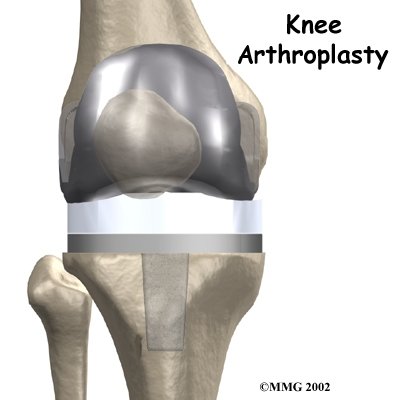

Artificial Joint Replacement of the Knee

A painful knee can severely affect your ability to lead a full, active life. Over the last 25 years, major advancements in artificial knee replacement have improved the outcome of the surgery greatly. Artificial knee replacement surgery (also called knee arthroplasty) is becoming increasingly common as the population of the world begins to age.